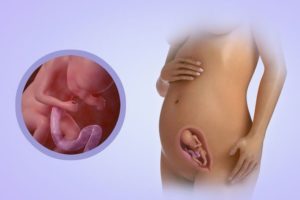

Что касается покалываний в матке при беременности на 14, 15, 20, 23 неделе и до конца второго триместра, то это происходит из-за активного роста органа. Он уже достиг внушительных размеров, и начал сдавливать все остальные внутренние органы. Это является вполне нормальным состоянием.

Очень часто встречаются покалывания в матке при беременности в 27 – 33 недели. Это связано с тем, что организм постепенно готовиться к родам. Покалывания в матке при беременности с 36 недель, в 37, 38, 39 и 40 недель возникает из-за периодического увеличения её тонуса. Данные ощущения более выражены, нежели ранее, так шейка органа готовится раскрыться, размягчается и немного сглаживается.

Ребенок на 18 неделе активно растет и развивается. Будущая мама начинает чувствовать нежные движения ребенка. Беременные с нетерпением ждут этого, так как первое шевеление является одним из самых волшебных событий в течение всей беременности.

Органы ребенка начинают функционировать с восемнадцатой недели беременности. В связи с этим женщина может испытывать некоторые спазмы и заметить белые, выделения из влагалища. Ребенок сейчас примерно 200 грамм и его рост около 1 сантиметров в длину. Его легочная и сосудистая системы стремительно развиваются.

Ребенок может глотать околоплодные воды и производить меконий. Меконий — первое испражнение, которое он сделает. Это хорошая новость, так как это значит, что его пищеварительная система начинает работать. На этой неделе развиваются отпечатки пальцев, создавая уникальный рисунок руки ребенка. Теперь еще больше кровеносных сосудов можно увидеть через его прозрачную кожу.

Если беременная еще не ощутила «бабочек» в животе, то сейчас это вполне возможно. Ребенок, безусловно, совершает удары ногами, руками, но, пока он еще не так силен.

Боли на 18 неделе беременности вполне нормальное явление. Растяжения коже, и рост живота могут вызвать боль и судороги в нижней части живота. Это пугает многих молодых мам, но это совершенно нормально. Боли на 18 неделе связаны с напряжением матки, и так как матка становится, все больше связки находятся в напряжении.

Боли в 18 недель беременности могут быть острыми и могут ощущаться по обе стороны от живота. Как правило, спазмы быстро утихают. Тем не менее, если на 18 неделе болит живот, то следует обратиться к врачу. Нужно обратить внимание как спазмы приходят и уходят, и насколько они регулярны, и какой между ними интервал.

Рост ребенка это тяжелый труд. Тело проходит через множество изменений в то время, когда ребенок растет. Беременность в 18 недель — болит живот, это происходит когда связки и мышцы вокруг матки начинают растягиваться. Как правило, растяжение можно почувствовать на одну или другую сторону. На 18 неделе боли могут проявляться и в пояснице, спине.